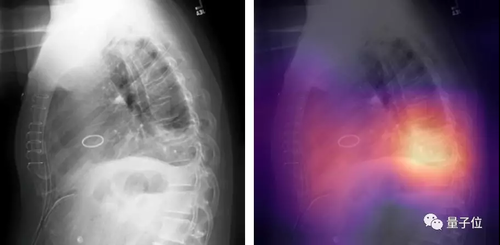

最近,吴恩达的斯坦福团队发布了一个叫做CheXpert的大型数据集,论文中选了AAAI 2019。

它包含了224,316张标注好的胸部X光片,以及放射科医师为每张胸片写的病理报告。

团队便是用这个数据集做Benchmark,举行了一场5种疾病的识别比赛。

用500张胸片的测试集来比,这个模型在心脏肥大、肺水肿以及胸腔积液这三项上,超越了前面提到的“另外3位人类医师”。